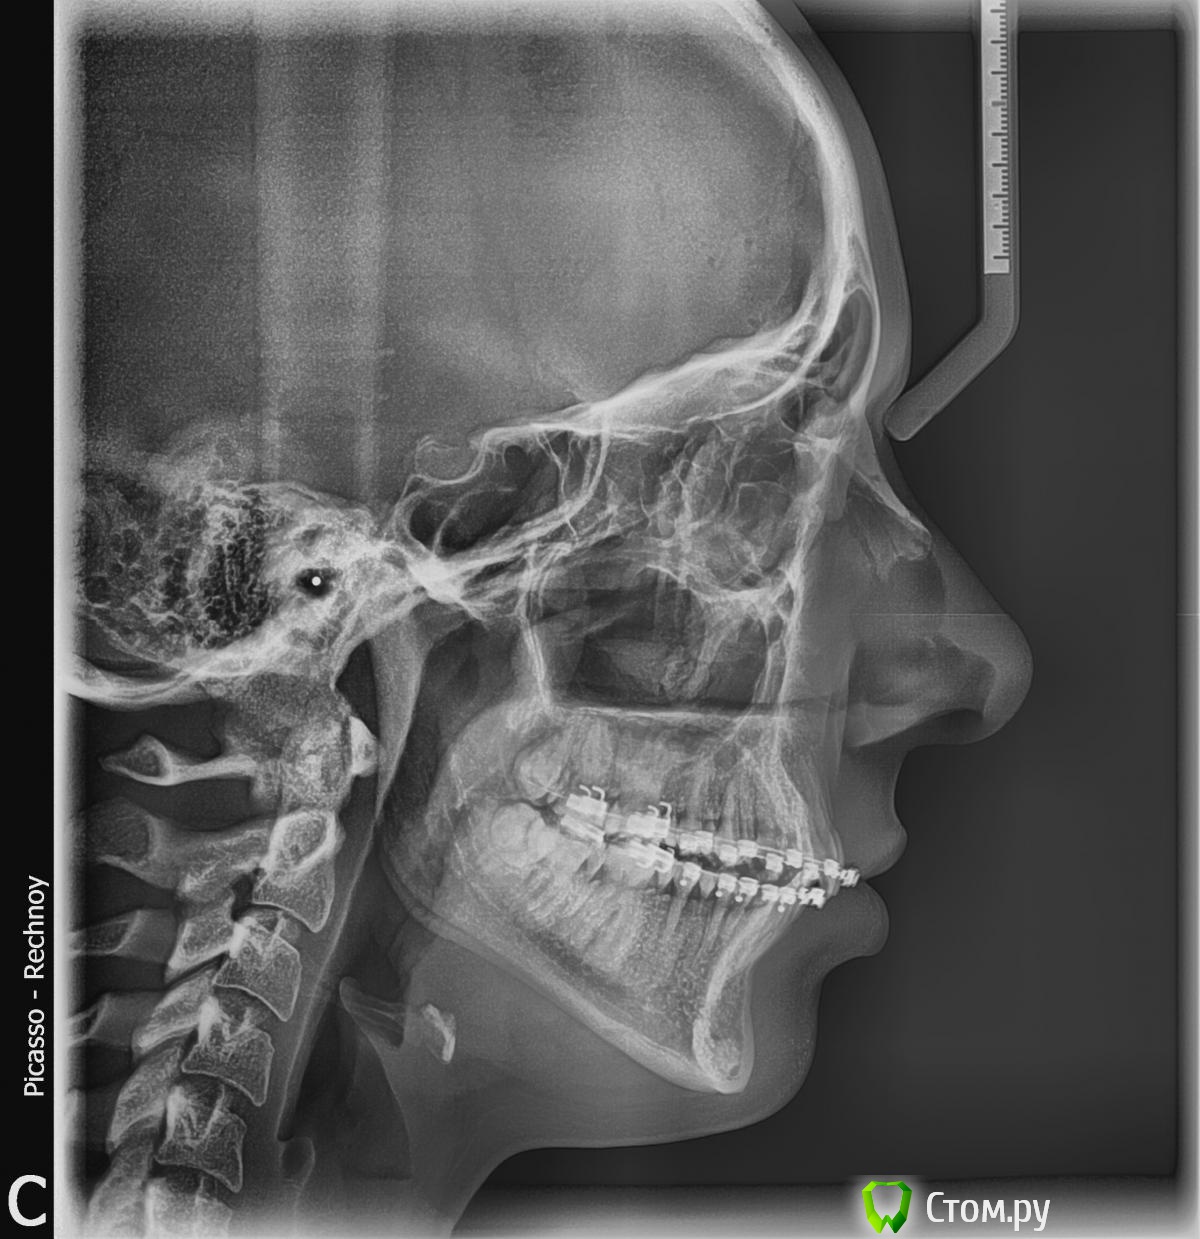

Ношу брекеты суммарно около года. Врач планирует заканчивать лечение через месяц-два - говорит, что зубной ряд ровный и что пора ставить жесткую стальную дугу.

Мне текущее положение вещей не очень нравится - какой-то некрасивый "наклон" зубов, очень разное расстояние от верхней губы до десны на всех зубах. В общем, сильная асимметрия, на мой взгляд.

Если нужны какие-то еще фотографии, постараюсь сделать и приложить. Сейчас есть рентгеновские снимки зубов, но они старые, полугодовой давности. Зубы мне не удаляли.

PS В самом деле, брекеты ношу уже окло трех лет, но два года "вхолостую", т.к. в студенческие годы просто не было денег на это дело. Врач говорит, пора снимать брекеты, зубы устали. Система damon 3.